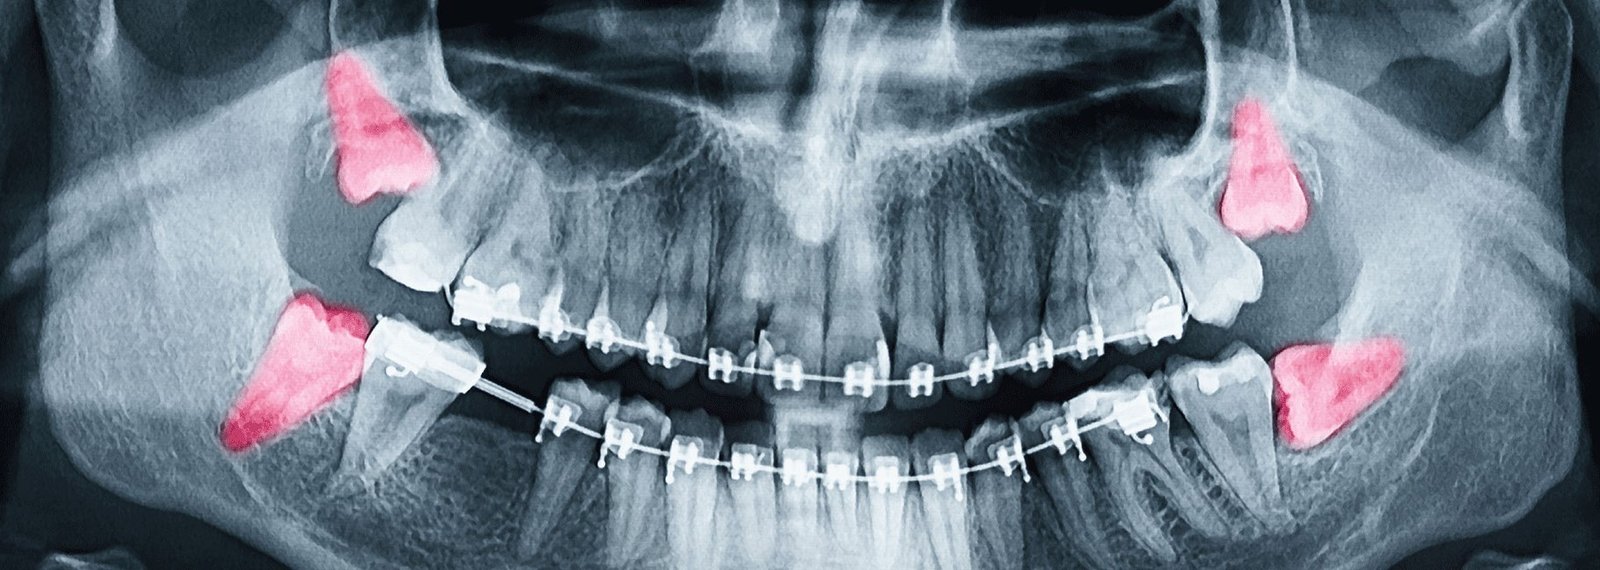

At Manchester Dental Practice, when we remove an impacted wisdom tooth, our highly trained dentists will take an X-ray to assess the tooth’s position in the gum first of all.

One of the most common procedures done in the UK, wisdom teeth removal refers to having one or more of large molars (your wisdom teeth) at the back of your mouth taken out. Sometimes, your wisdom teeth don’t come through properly, causing problems such as soreness, inflammation and decay. Having wisdom teeth taken out can remedy these symptoms.

For most people, they are the last teeth to emerge usually in the mid-twenties. By the time your wisdom teeth come through, there may not be enough space in your mouth for them to grow well. This causes an “impacted” wisdom tooth- where it gets partially stuck in your gums, or grows at an angle.

If an impacted wisdom tooth grows in an unhealthy way, food and bacteria can get trapped around the gum causing soreness, tooth decay and infection.